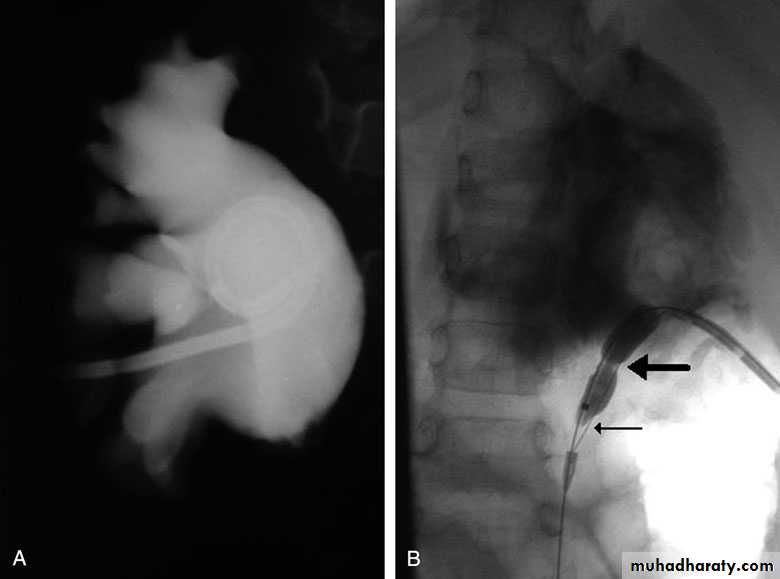

Postcaval (Retrocaval) ureter (Preureteral Vena Cava )

The right ureter pass behind the inferior vena cava

This might causes obstruction

Vascular abnormality

Incidence: about 1 in 1500Although it is congenital, most patients present at 3rd or 4th decade.

Diagnosis: IVU

Treatment:

surgical correction involves ureteral division, with relocation and ureteroureteral or ureteropelvic reanastomosis,

usually with excision or bypass of the retrocaval segment, which can

be aperistaltic